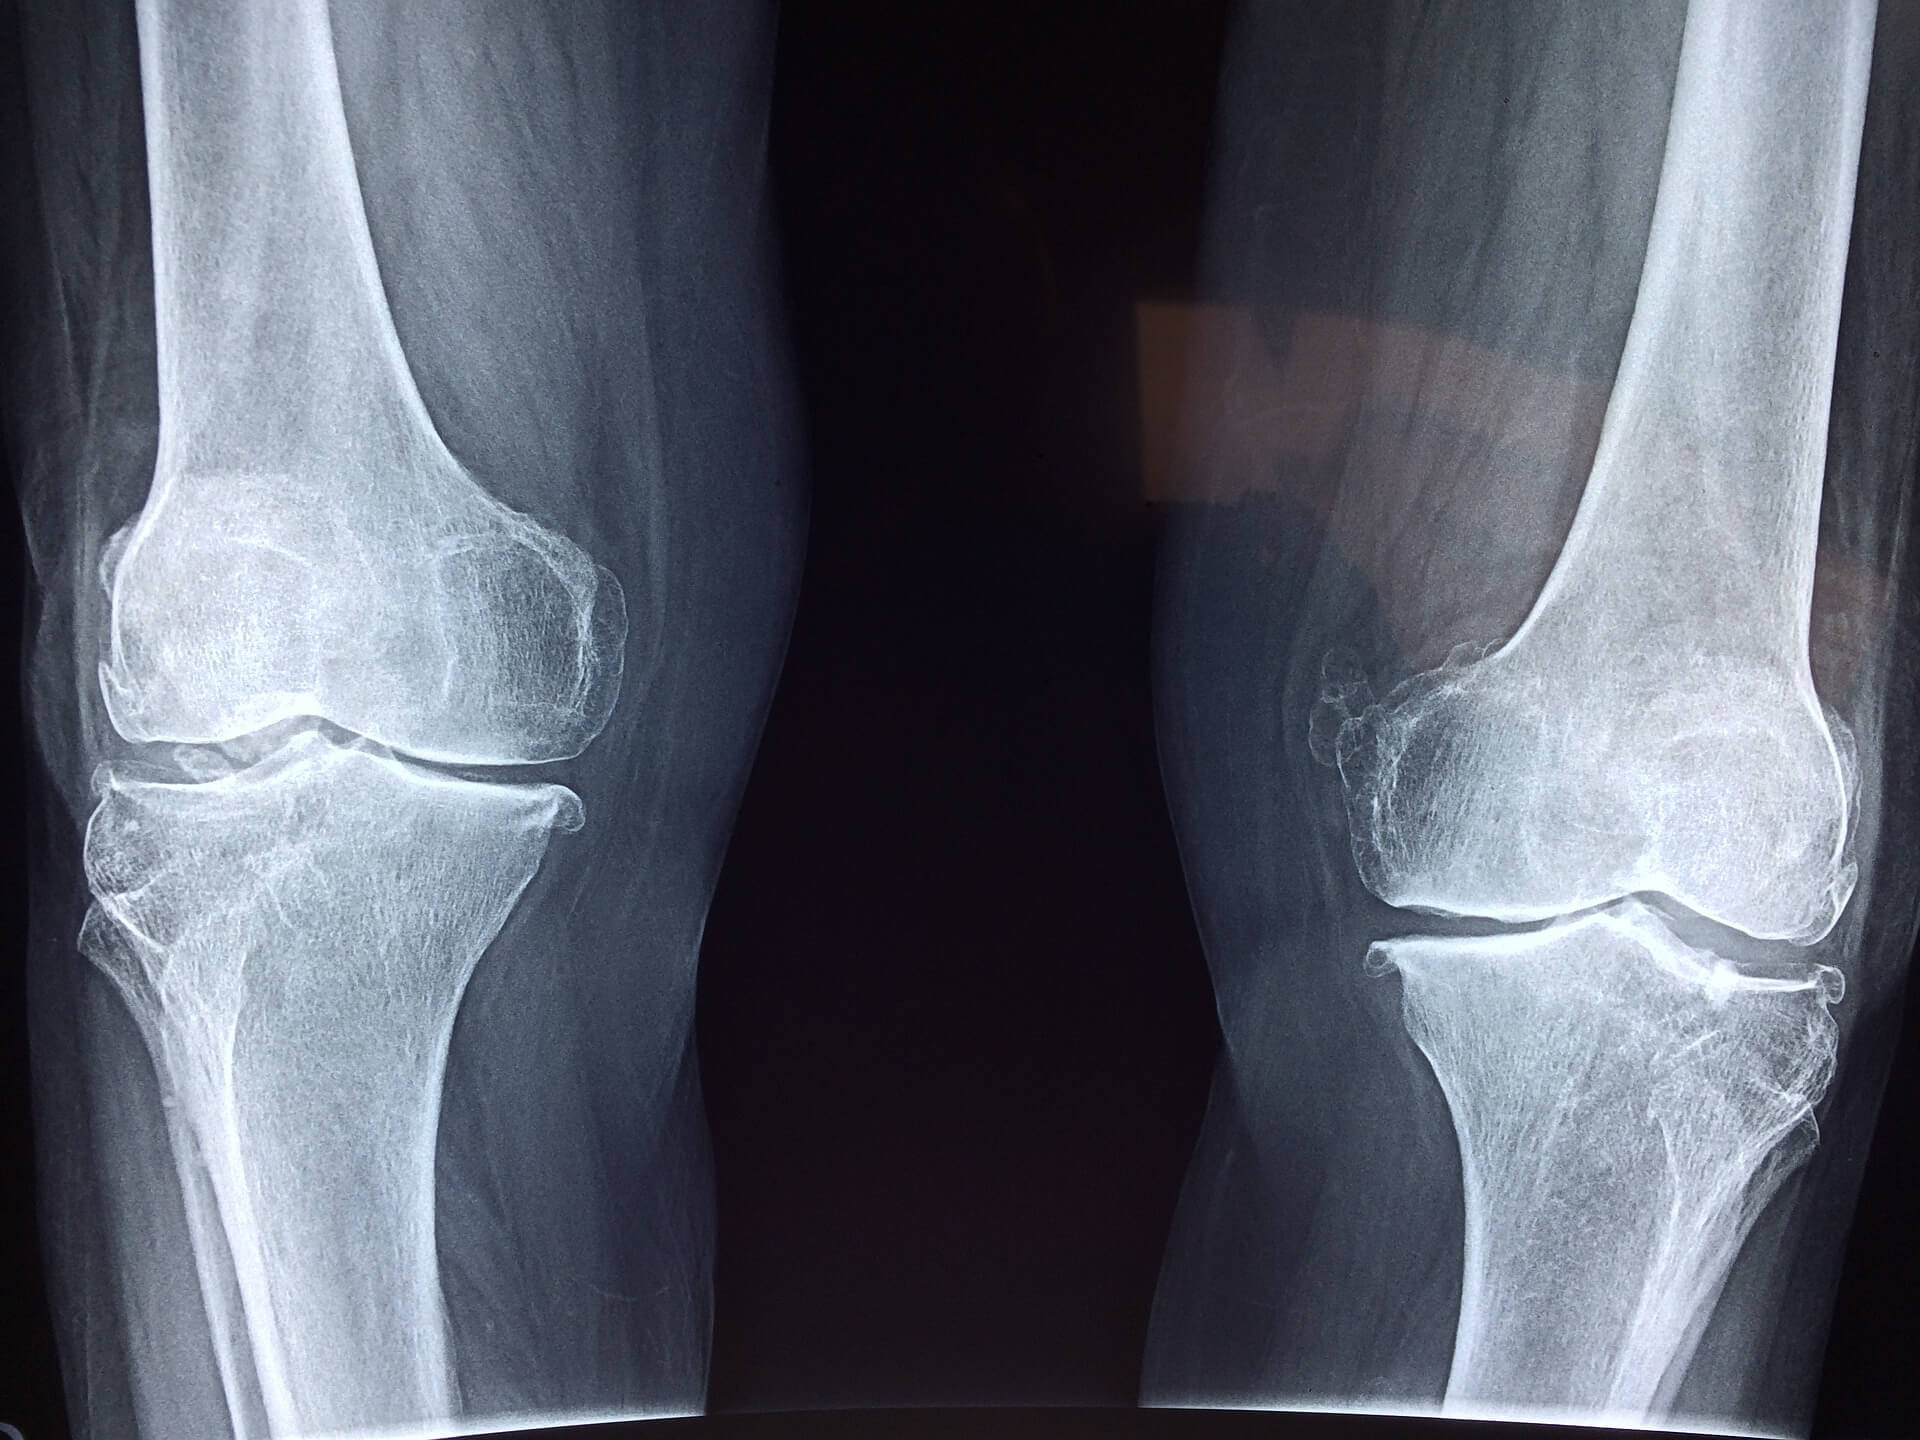

관절염은 어떻게 개선할 수 있을까? 관절염이란? 관절염은 관절의 급성 또는 만성 염증이 특성입니다. 증상은 대개 관절통증, 뻣뻣함, 변형이 있는데요. 따라서 이 질병은 온갖 종류의 병리와 류